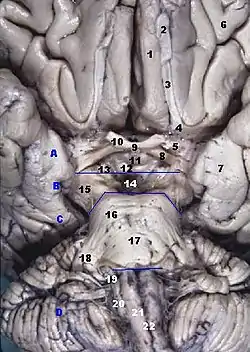

Transformations of the visual field toward the visual map on the primary visual cortex. Brain and brainstem seen from below

Brain and brainstem seen from below Left hemisphere of the brain seen in a cadaveric specimen from the side, with the optic chiasm labelled.